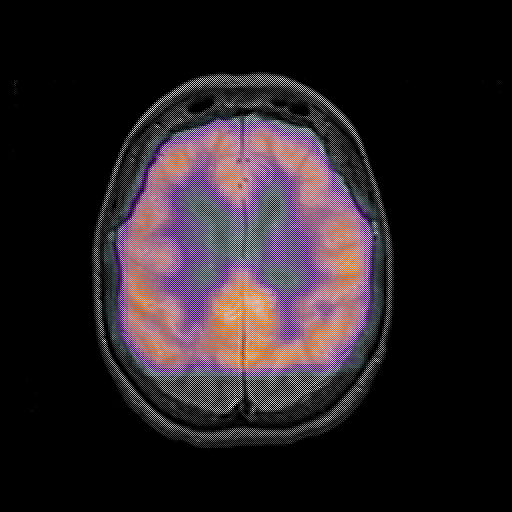

overlay : Slice 37

Slice 37

MRCBFCBF with

T1PDT2T1PDT2